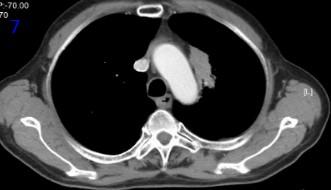

2021年8月30日,放療后9個月,胸部CT可見左肺腫瘤較2021年3月19日明顯增大(圖5), RECIST評價,PD。

圖5放療后9個月胸部CT